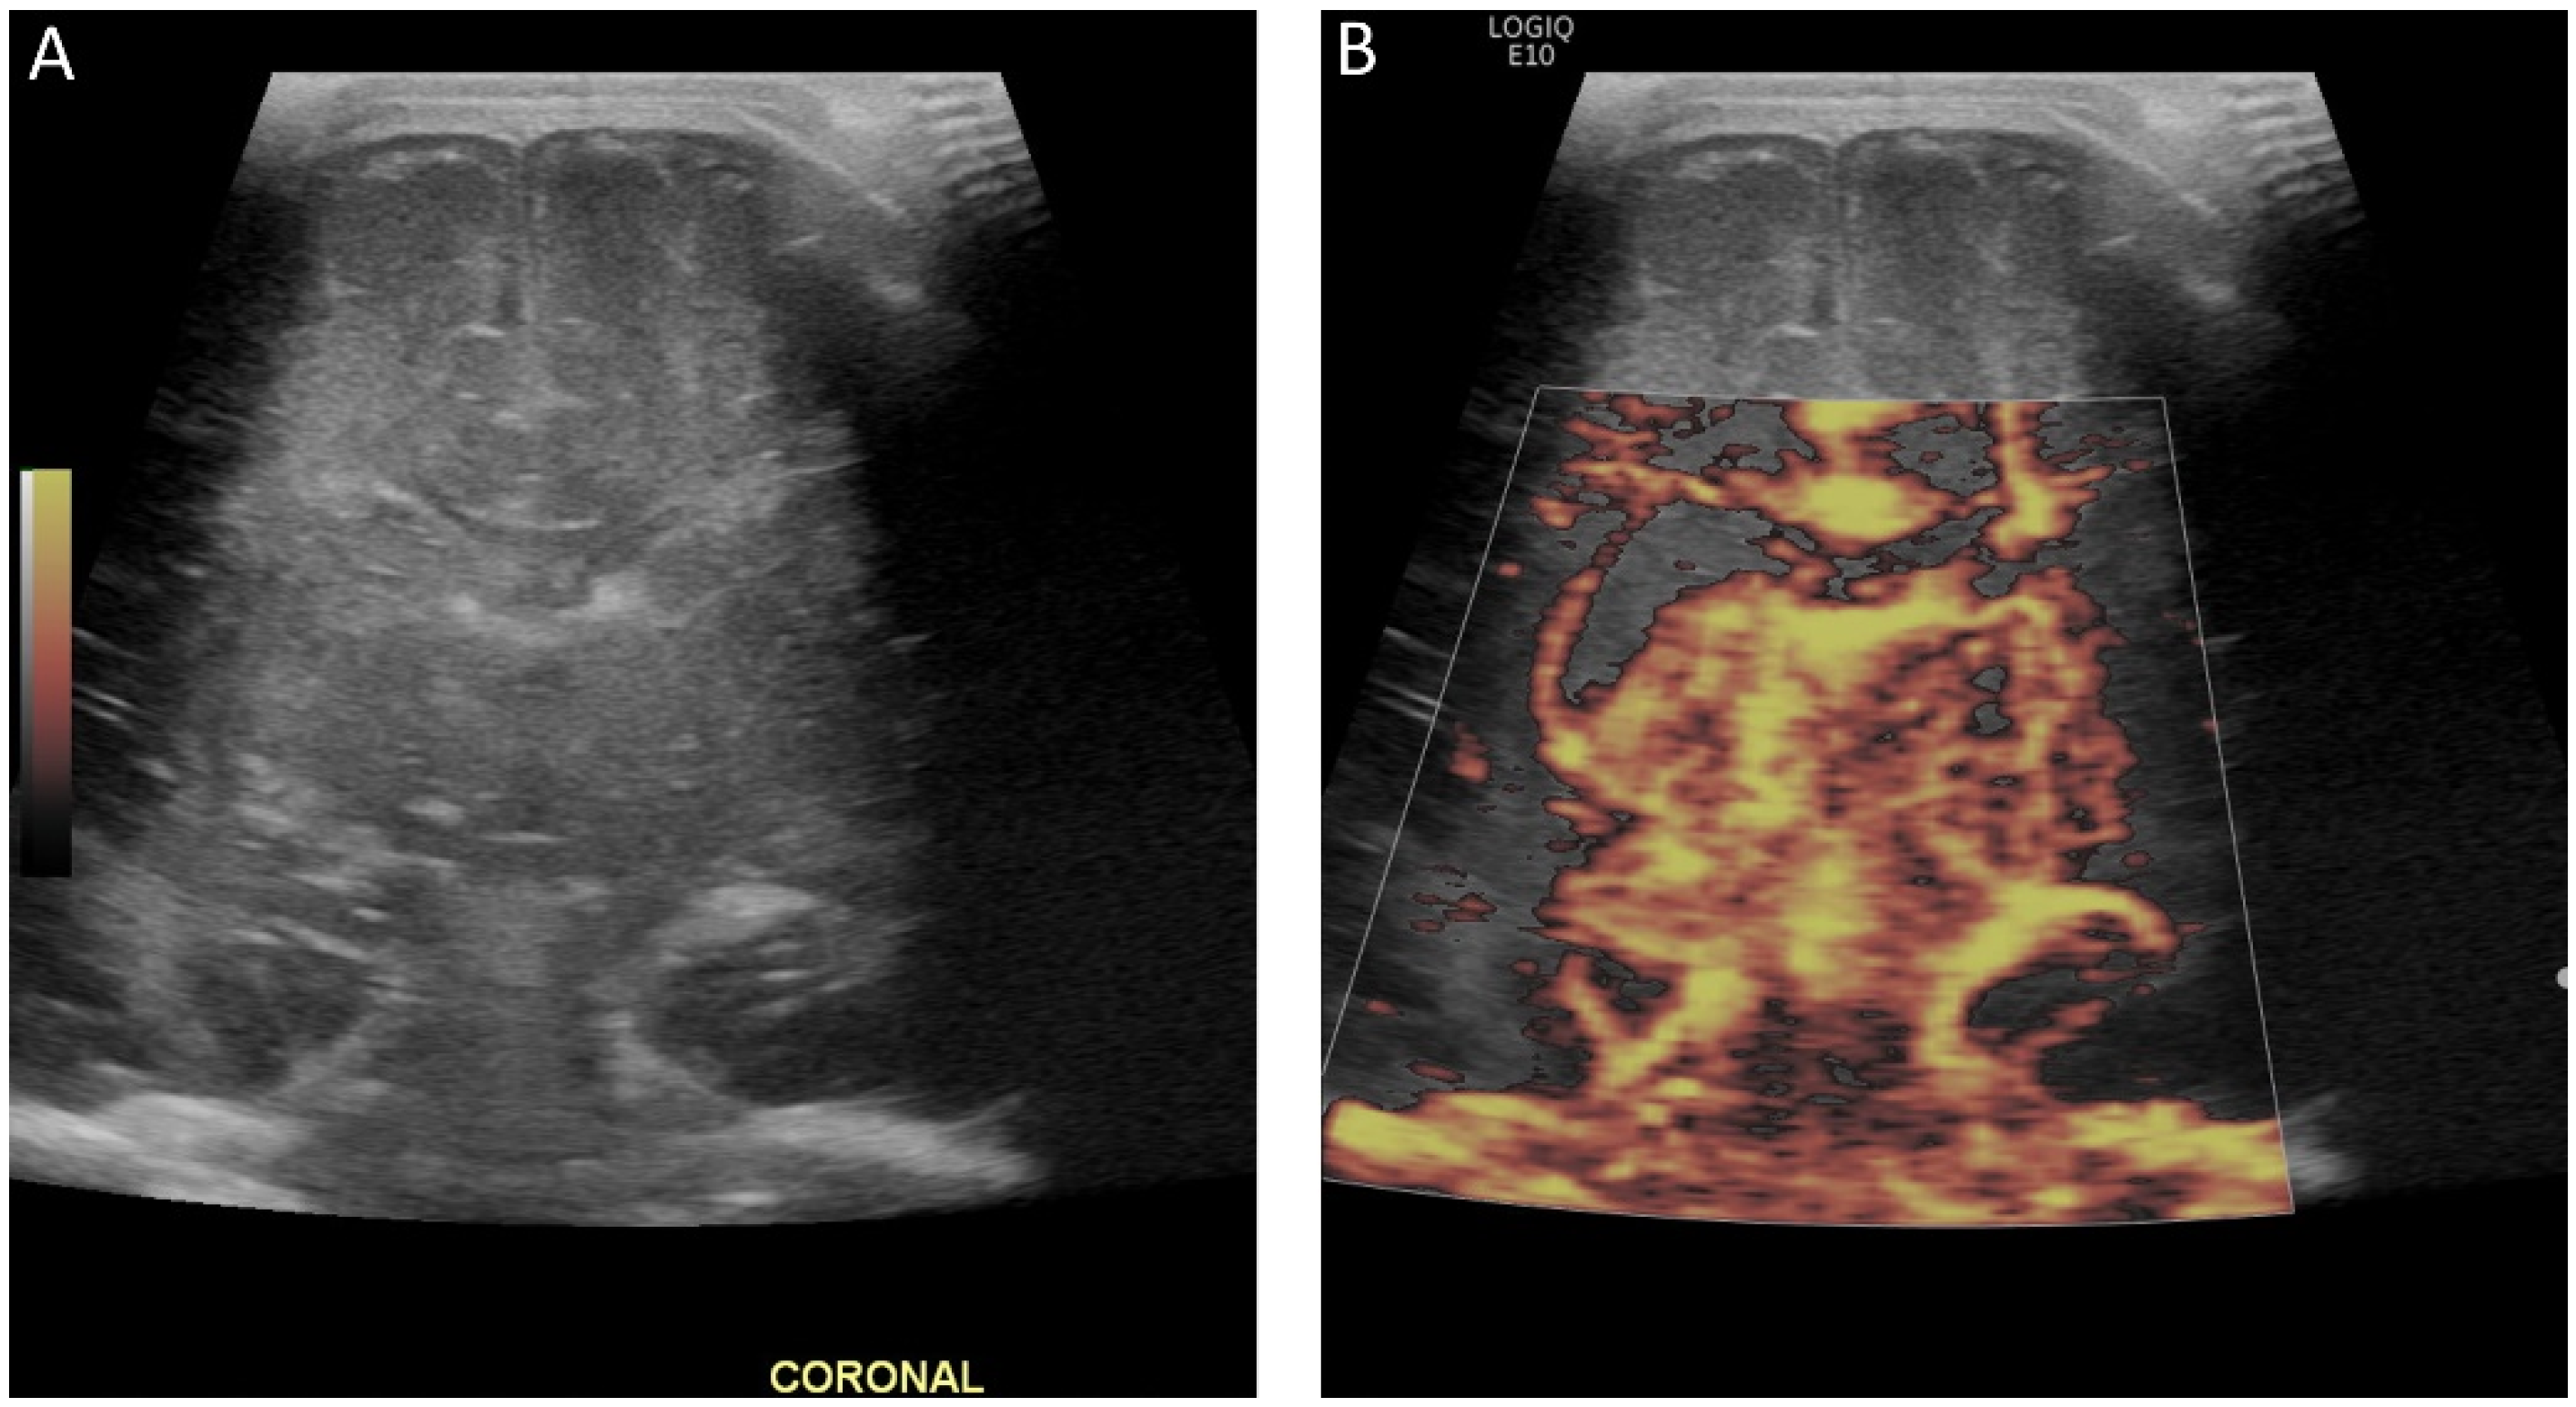

Brain tissue stiffness is also affected by hydrocephalus (Figure 8). In a prospective study using SWE, the brain stiffness of healthy neonates was compared to that of neonates with hydrocephalus [65]. Hydrocephalus was associated with greater tissue stiffness, and SWE measurements were positively correlated with intracranial pressure [65]. Transtemporal SWE in adults shows a similar correlation between stiffness and intracranial pressure [54], and this may be a viable approach in children with closed fontanelles.

Figure 8.

Ultrasound elastography of a 2 month old, former 28 week and 4 day infant with posthemorrhagic hydrocephalus after shunt placement. (A) A grayscale image demonstrating a right shunt catheter terminating in the right frontal horn. Periventricular cystic changes are seen related to prior infarct. Elastography measurements were taken over (B) the right basal ganglia, with values of 1.55 m/s and (C) the periventricular white matter with values of 2.18 m/s (C). These images were initially published in Pediatric Neurology, Volume 86, by authors Danielle deCampo MD PhD and Misun Hwang MD in the article “Characterizing the neonatal brain with ultrasound elastography,” pages 19–26, Copyright Elsevier (2018).